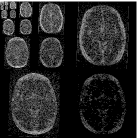

Table 3 shows the SNR values for different reconstructions and Figure 6 shows reconstruction results visually, at acceleration factor of 4 (25% of the k-space). In this case, there are major changes between the baseline and the follow-up scans due to therapy response. As a result, TCS-MRI exhibits poor performance in the vicinity of the changing tumor, since it is partially based on similarity between the consecutive scans, an assumption which is not valid in this case.

LACS-MRI, however, convergences to a result which is similar to CS-MRI. This is obtained thanks to the adaptive sampling and the weighting mechanism embedded in LACS-MRI, which reduces the weight given to the similarity to prior scan in the reconstruction process, if such a similarity does not exist.

Nyquist sampling (baseline)

Nyquist sampling (follow-up)

CS-MRI (follow-up)

TCS-MRI (follow-up)

LACS-MRI (follow-up)

Reconstruction result

Difference image

Reconstruction (zoom)